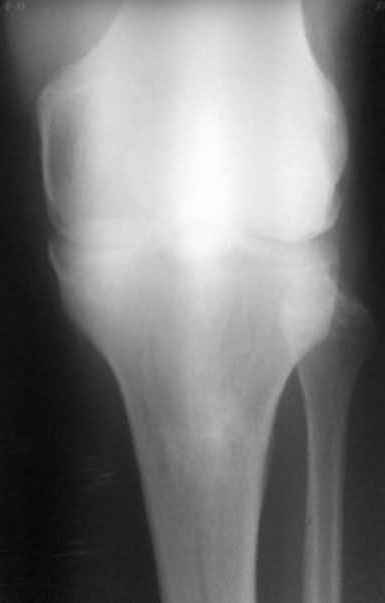

пациент наконец то объявился вновь и мы смогли выполнить новые снимки как лежа так и в нагрузке

если у вас остались силы, давайте обсудим

Уважаемый доктор Зайцев! Причина деформации проксимальной тибии у Вашего пациента - преждевременное и несимметричное закрытие зоны роста передней части проксимальной ростковой зоны б/б кости в следствии окультной травмы произошедшей в возрате 10-12 лет. Есть 2 причины рекурвационной деформации в области коленного сустава - мягкотканевая и костная.В данном случае Вы имеете дело не с рукурвацией коленного сустава, а с рекурвационной деформацией проксимальной голени. "Заднего выдвижного положения" на самом деле нет.То, что Вы видите на боковом снимке - это не задний подвывих голени - это снимок, сделанный в сгибании коленного сустава. Дело в том, что костные дефорсации в области коленного хорошо компенсируются за счёт движения в суставе. поэтому то, что вы видите, как задний подвывих на самом деле - сгибательное положение колена.

Это можно проверить очень просто - надо сделать стресс рентгенограмму в положении полного разгибания коленного сустава.Для этого посадите больного на стул, пятку поставьте на другой стул, дайте пациенту кассету 30Х40 держать с наружной стороны колена, и попросить ренгентехника сделать латеральный снимок с втутренней стороны. Сделав снимок здорового колена, Вы сможете расчитать деформацию.

Соответственно, для планирования коррекции необходимы сравнительные функциональные рентгенограммы, т.е. профиль в максимальном разгибании коленных суставов.

Если суставная площадка tibia занимает при "переразгибании" колена то же положение, что будет видно на здоровом суставе, то при коррекции формы tibia компенсаторная сгибательная установка коленного сустава самоликвидируется. Опора на бедро и прочее будет избыточно. По-моему, там именно такая ситуация.